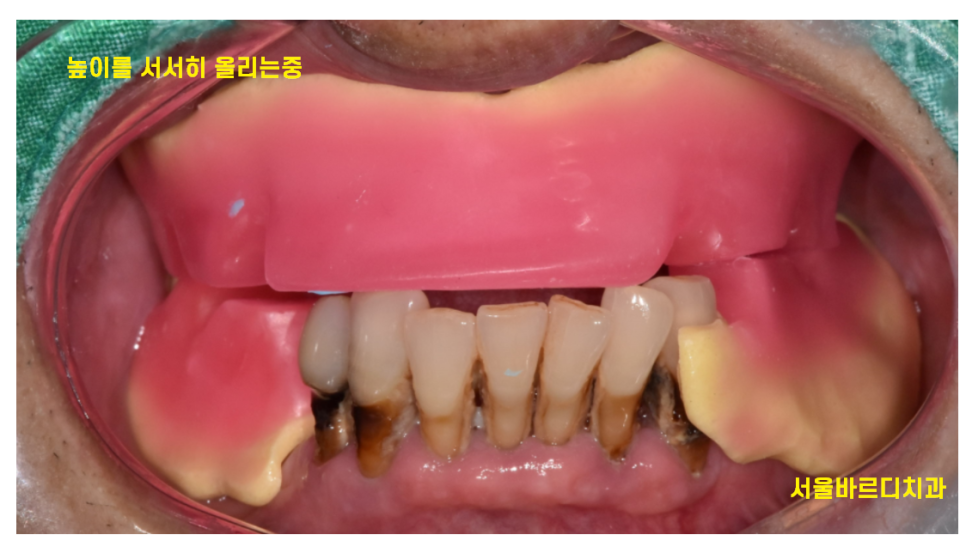

231103

해당 환자분도 임플란트를 무작정 심기보다

높이를 먼저 올려 적응하는 단계를 가졌습니다.

그동안은 임시틀니를 사용하시면서 지냈는데요.

틀니에서 임플란트로 전환할 때 환자들이 적응하는 데 시간이 걸려요ㅠㅠ

윗니와 아랫니가 닿던거를 높여버리니

씹는 느낌도 달라지고

발음도 잘 안된다고 해주시거든요

충분한 적응기간을 거친 후에

임플란트 식립을 진행하게됩니다.